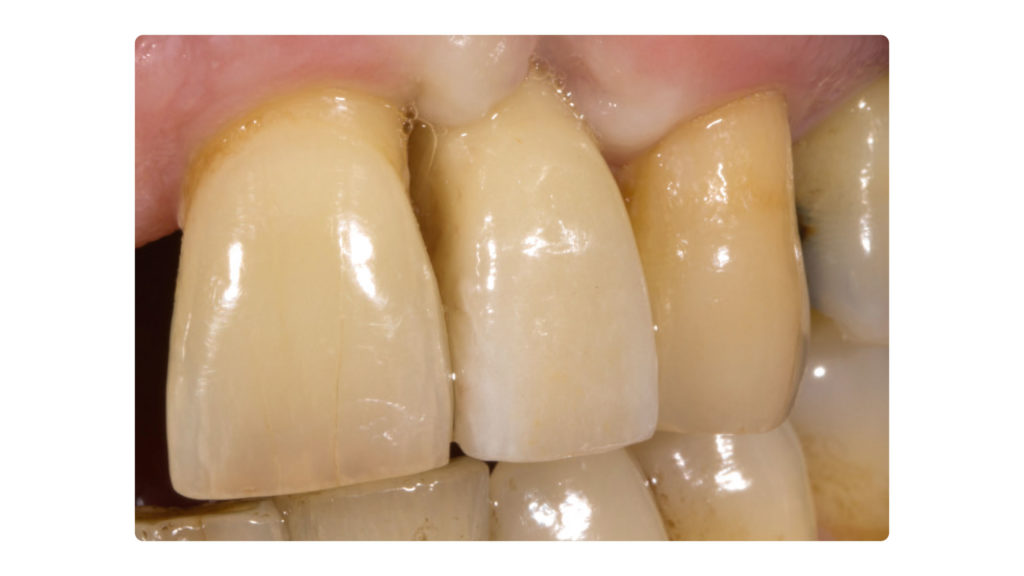

Rohbrandeinprobe

Bei der Rohbrandeinprobe stellten wir einen leichten Helligkeitsunterschied zwischen der Restauration und unserem Referenzzahn 21 fest. Am auffälligsten zeigte sich diese Abweichung insbesondere am inzisalen Drittel und an den Rändern (Abb. 30a bis c). Zur Dokumentation der Farbabweichung und dezidierten Farbauswahl wurden daher im Rahmen der Rohbrandeinprobe nochmals Fotos angefertigt. In diesem Fall kamen die Farben B4, A4 und D2 den natürlichen Zähnen am nächsten. Und auch der zuvor gewählte Schmelz musste aufgrund der falschen Helligkeit und Transluzenz verändert und die Effekte im inzisalen Drittel verstärkt werden (Abb. 31a bis c). Insbesondere die Leuchtkraft und Transluzenz, aber auch die Transluzenz und Sättigung des rot-orangen Opaleszenz-Effekts im Bereich der Mamelons des natürlichen Zahnschmelzes sowie die „gefürchteten“ Schmelzrisse wussten zu beeindrucken und galt es bei der Rekonstruktion zu beachten.